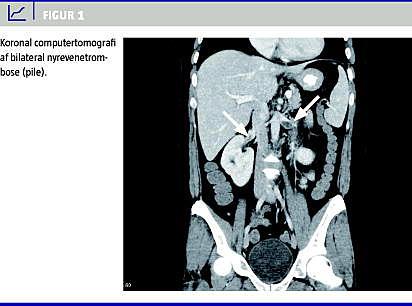

Hun blev overflyttet til en hæmatologisk afdeling, hvor resultaterne af en knoglemarvsbiopsi viste, at der var tale om akut myeloid leukæmi (AML). Ved en senere computertomografi (CT) af abdomen foretaget med intravenøs kontrastvæske sås bilateral nyrevenetrombose (Figur 1 ), formentlig pga. koagulopati, der var forårsaget af leukæmien.

En efterfølgende subakut CT af abdomen viste bilateral nyrevenetrombose (Figur 1), som blev tolket som koagulopati, der var forårsaget af leukæmien, og patienten blev sat i behandling med tinzaparin [1].